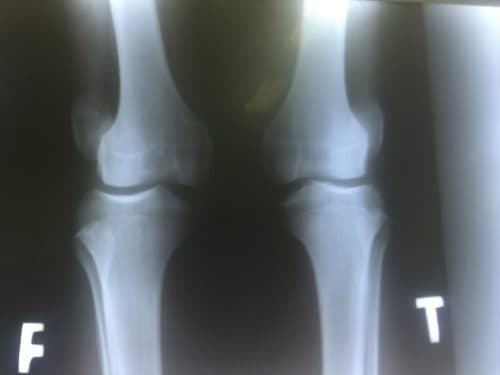

Dấu hiệu rách sụn chêm đầu gối là gì?

Sụn chêm là thành phần quan trọng ở đầu gối và rất dễ rách khi bị tai nạn hoặc chấn thương khi chơi thể thao. Vậy dấu hiệu rách sụn chêm đầu gối là gì? Dấu hiệu rách sụn chêm đầu gối là gì? Sụn chêm là một trong những thành phần quan trọng của […]